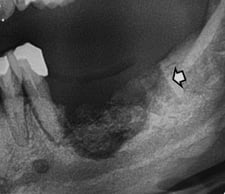

画像診断における「予兆」を見逃さないことが強調されました:

- **歯根膜腔の拡大**(歯がぐらぐらし始める)

- **骨硬化像を伴う根尖病変**

- **不適合義歯による潰瘍**

これらの予兆を早期に発見し、対応することが重要です。